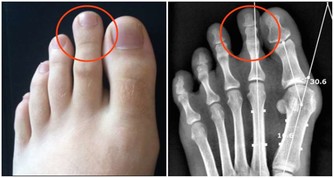

在這裡就給經常腿痛的女士推薦一個方法吧。到藥店裡買一些透骨草,每天晚上取60克,加適量的清水,熬上半小時,煮好後把藥汁倒入洗腳盆,先不用急著加涼水,可以先用熱氣蒸薰一下膝關節和踝關節。然後拿兩個毛巾,用藥水浸濕,稍微擰一擰,疊成塊兒狀放在膝蓋上進行熱敷,每晚敷20分鐘左右即可。等藥水的溫度降到40度左右的時候,用剩下的藥水把膝關節洗一洗。

由於人體的關節部位腠理比較疏鬆,所以風、寒、濕等邪氣很容易入侵。也正因為這個原因,藥效也比較容易滲入,所以以上熏洗、熱敷的效果也會比較理想。另外,熏泡完之後,你可以把腳踝和腳指都搓一搓,搓到發熱、發紅為止,這能幫助你打通經絡、驅除寒氣。如果家裡有足浴桶,還可以用這個藥水泡泡腳。